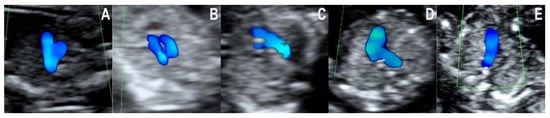

- Normal diastolic filling of both ventricles with an abnormal cardiac axis rotated to the left and one mediastinal vessel with curved course. All of the tetralogy of Fallot (TOF) and the double outlet right ventricle (DORV) cases in our collection respected this pattern. We found that the first trimester diagnosis was not difficult in the presence of the obviously abnormal curved, boomerang-like, trans-mediastinal vessel. On the other hand, we found it difficult to further differentiate between TOF and DORV (with no transposition of arteries) in early pregnancy. Based on the images analyzed, we think that DORV with transposed vessels might be distinguished from other lesions from the TOF spectrum on the basis of the longer trans-mediastinal course of the abnormal vessel.